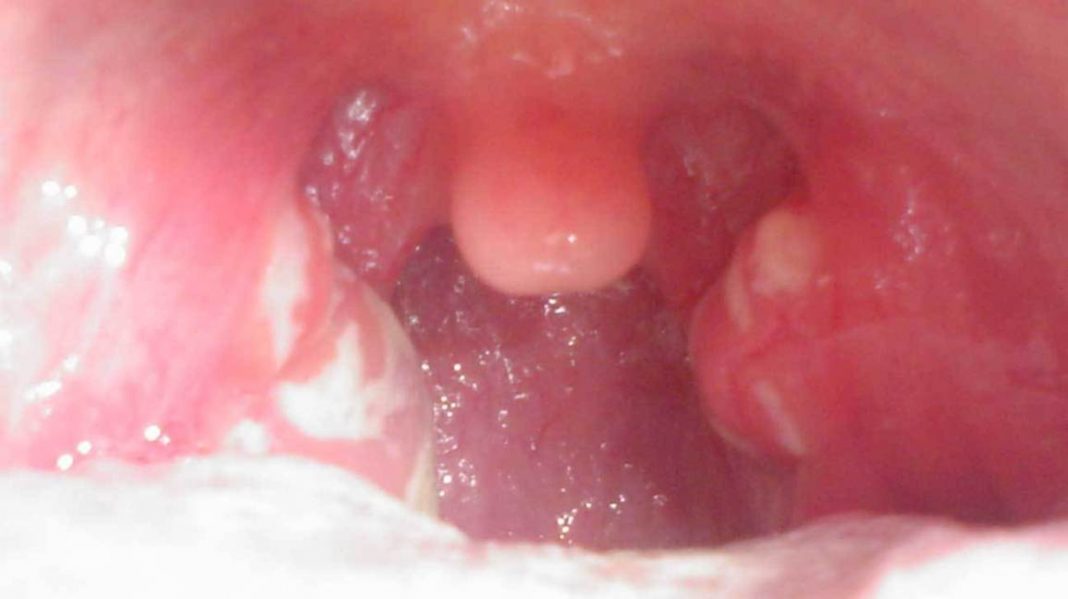

En muchas ocasiones un bulto en el cuello no se debe solamente a los ganglios inflamados sino que lo originan otras causas, que hacen que el mismo se presente.

Por ello es muy importante determinar que lo origina para su posterior tratamiento y curación, a veces estas otras razones son muy fáciles de determinar e incluso tratar y otras algo más complejas pero lo importante es determinar que lo ocasiona.